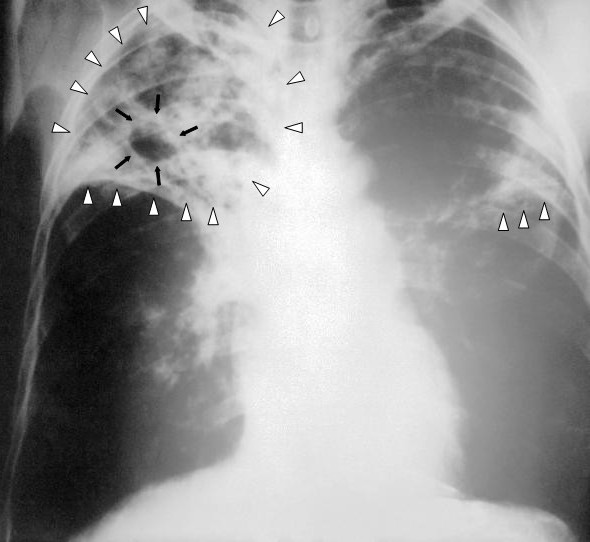

X-ray of a patient with advanced pulmonary tuberculosis.Credit: Centers for Disease Control via <a href="http://commons.wikimedia.org/wiki/File:Tuberculosis-x-ray-1.jpg">Wikimedia Commons</a>.

At least 12 patients in Mumbai, India, have been infected with a totally drug-resistant form of tuberculosis. One has died.

Tuberculosis, which kills around 1,000 people a day in India, has acquired a deadlier edge. A new entity-ominously called Totally Drug-Resistant TB (TDR-TB )-has been isolated in the fluid samples of 12 TB patients in the past three months alone at Hinduja Hospital at Mahim [in Mumbai]. The hospital’s laboratory has been certified by the World Health Organization (WHO) to test TB patients for drug resistance. While Iran first reported TDR-TB cases three years ago, India seems to be only the second country to report this deadly form of the disease. TDR-TB is the result of the latest mutation of the bacilli after Multi-Drug-Resistant TB (MDR-TB ) and Extremely Drug-Resistant TB (XDR-TB ) were diagnosed earlier.

[A] condition in which patients do not respond to any TB medication… The mortality rate for this strain of the infectious disease is 100%… The patients, including a 13-year-old girl were diagnosed in October. A 31-year-old woman from Dharavi died in November… Doctors treating these patients say the absolute resistance is a result of the patients being prescribed wrong antibiotics by unspecialised doctors.

TB is already one of the world’s worth killers, up there with malaria and HIV/AIDS, accounting for 9.4 million cases and 1.7 million deaths in 2009… At the best of times, TB treatment is difficult, requiring at least 6 months of pill combinations that have unpleasant side effects and must be taken long after the patient begins to feel well. Because of the mismatch between treatment and symptoms, people often don’t take their full course of drugs.

The CID letter reports inadequate care provided to four of the 12 Indian patients, who saw as many as four different doctors, and at least three received partial, multiple courses of the wrong antibiotics:

A study that we conducted in Mumbai showed that only 5 of 106 private practitioners practicing in a crowded area called Dharavi could prescribe a correct prescription for a hypothetical patient with MDR tuberculosis. The majority of prescriptions were inappropriate and would only have served to further amplify resistance, converting MDR tuberculosis to XDR tuberculosis and TDR tuberculosis.

Worryingly, the first emergence of totally drug-resistant TB seen in 15 patients in Iran in 2009 included Afghani, Azerbaijani, and Iraqi immigrants, writes McKenna. Many health workers at the time assumed the total number of cases was higher than diagnosed, since there was (and is) little in the way of even basic medical care in those border areas.

Worldwide, only two-thirds of countries with resistant TB have the labs to diagnose those strains, with only 10 percent of multi-drug-resistant TB patients receiving treatment, at cure rates as low as 25 percent. There’s no cure for totally drug-resistant TB.